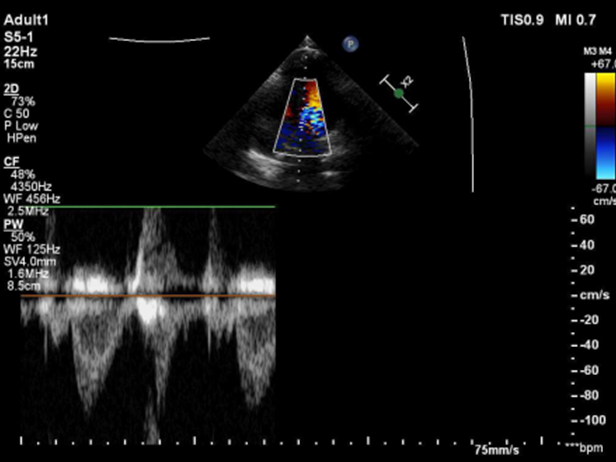

超声多切面确认

封堵器骑跨房间隔两侧

五腔心切面

剑下双房心切面

四腔心切面

主动脉短轴切面

封堵器呈“Y”字形牢牢抱住主动脉,夹持缺损

封堵器释放后形态良好

未见残余分流,封堵成功